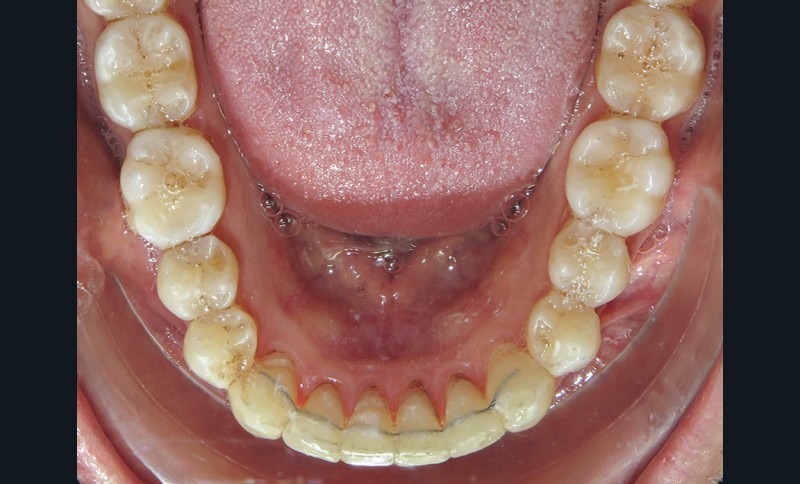

Une fois le sens transversal traité, la correction s’est portée sur le décalage sagittal de Classe II au niveau dentaire (fig. 3). La présence de tip forward sur les dents des secteurs latéraux maxillaires signifie que les apex de ces dents sont plus ou moins bien placés. Des mouvements de version sont suffisants. C’est pourquoi a été retenue la solution suivante :

- collage au maxillaire d’un segment d’arc acier 019 x 025 (traité au rhodium à des fins esthétiques) sur les canines et les premières molaires maxillaires avec du composite (contenu dans une carpule) destiné au collage des fils contention (choisi pour sa résistance et sa facilité de mise en œuvre) ;

- réalisation d’une gouttière mandibulaire rigide englobant l’ensemble des dents mandibulaires. Cette gouttière a pour but de relier l’ensemble des dents de l’arcade inférieure (ancrage) et d’obtenir une désocclusion.

- collage de boutons sur les 13 et 23 (en composite pour améliorer l’esthétique) et de boutons métalliques (pour le confort) sur les 36 46

- port d’élastiques (3/16 4,5 Oz) reliant les boutons maxillaires à ceux mandibulaires pour obtenir une force de recul sur l’arcade supérieure et d’avancée sur l’arcade opposée (les mouvements ont été facilités par les extractions des 18 28). Les prémolaires n’étant pas collées, le mouvement généré est un mouvement de version et donc de redressement (car tipées au départ). Il est à noter que les boutons canins sont collés le plus cervicalement possible pour avoir une traction oblique avec les élastiques inter-arcades, afin d’avoir un mouvement de descente des canines supérieures qui sont trop hautes. L’intérêt d’avoir une gouttière mandibulaire par rapport à un arc lingual ou un dispositif multi-attaches, c’est qu’une gouttière contrôle mieux les mouvements de vestibulo-version des incisives mandibulaires induits par les élastiques.